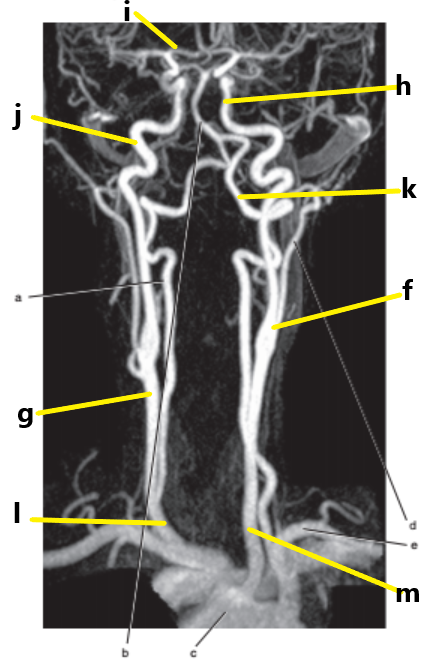

What is letter i ?

Anterior cerebral artery

What is letter m ?

Common carotid artery

What is letter j ?

Internal carotid artery

What is letter g ?

What is letter a ?

Vertebral artery

What is letter h ?

Internal jugular vein

What is letter k ?

What is letter f ?

Carotid bifurcation is -

superior border of thyroid cartilage

The common carotid artery bifurcates at the level of -

C3-C4

What is letter l ?

Common carotid

What is letter e ?

Basilar artery

Carotid sinus/bifurcation